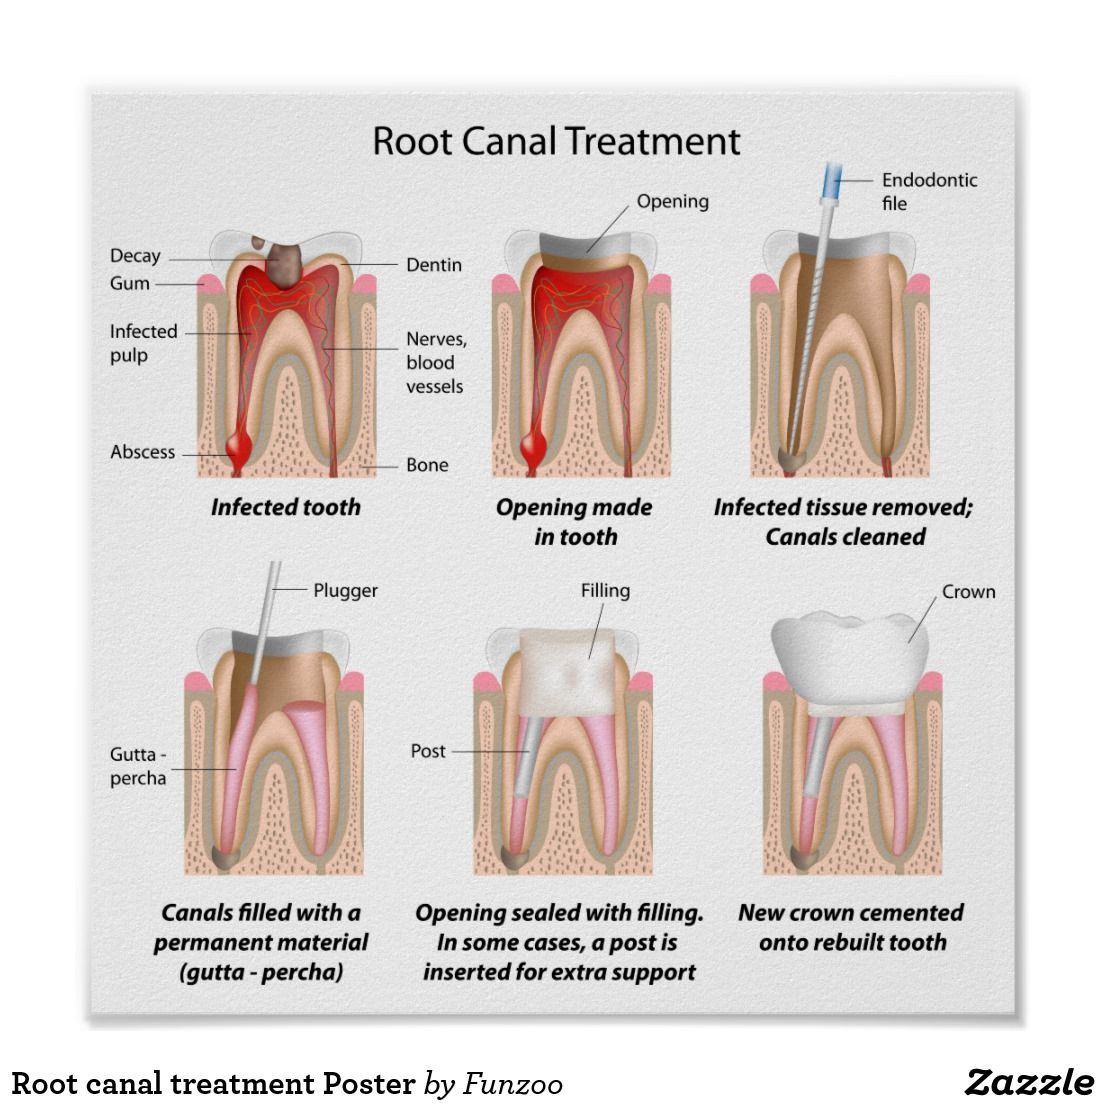

Root Canal Treatment

Root Canal Treatment is a procedure performed on the infected tooth to remove the decay affecting the pulp (underlying tissue containing blood vessels and nerve supply to a tooth). Simple filling procedure cannot restore a tooth’s dental health when the infection has encroached the pulp. Root canal therapy is the only alternative to save such tooth from being extracted. The main objective of root canal treatment is to preserve the infected existing natural tooth by disinfection. During a root canal therapy, access to the root canal present inside the root of a tooth is gained and the infected tissue is removed entirely. Hence Root Canal treatment bypasses extraction of the infected tooth and its replacement procedures thereby saving time and money.